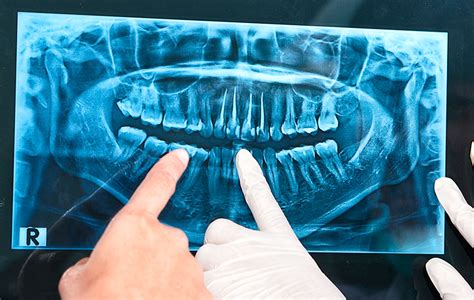

La ortopantomografía, o radiografía dental panorámica, es el tipo más común de radiografía dental. De hecho, lo más corriente es que se efectúe en la primera visita del paciente a la clínica, durante su revisión general. Con un aparato de rayos X, se toma una imagen completa de la boca del paciente. Aporta una imagen plana de la boca completa del paciente. Aportan mucha información y se usa en todas las ramas de la odontología.

Gracias a las ortopantomografías, los dentistas pueden identificar patologías y anomalías en las raíces dentales o en dientes incluidos: que no han erupcionado de la encía. Por ejemplo, podemos estudiar de manera general el número de dientes presentes, su posición y su forma o, por el contrario, si hay dientes que aún no han erupcionado, nos ayuda a saber su grado de maduración o la trayectoria eruptiva que siguen, el espacio con el que cuentan para colocarse en su lugar, o si están ausentes retenidos o impactados.

Nos permiten ver el número, tamaño y la forma de las raíces o detectar cualquier anomalía o lesión a este nivel si la hubiera. También, de forma genérica y sin mucho detalle, el nivel de hueso existente. Como último ejemplo, deciros que nos permite diagnosticar algunas caries, infecciones e incluso la presencia de sarro subgingival.

Ejemplo de radiografía panorámica dental